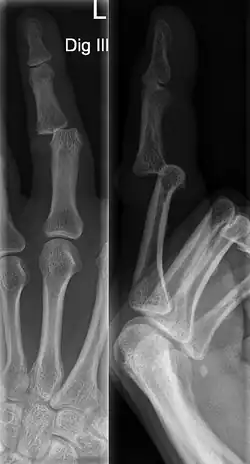

There are a variety of possible signs indicating a jammed finger. These depend on the severity of the injury.[3] They may include swelling, reduced joint flexibility, pain, tenderness, and joint deformity.[1] There may also be discoloration of the skin due to bruising. These symptoms usually persist for a few weeks.[3] In some cases, the damage and its effects can last for years.[4] Initial signs of a dislocation include abnormal bumps or projections at the joint. There may also be an audible popping noise when the injury occurs.[5] Fractures are indicated by abnormal protrusions along the bone,[6] where the bone itself appears split or twisted.

A jammed finger can generally be diagnosed by a physical examination. Bone or joint deformity may indicate potential dislocations or fractures.[6] The basic structure of the finger includes three bones with joints in between each.[9] The joint closest to the tip is the distal interphalangeal (DIP) joint. The next joint, moving closer to the hand, is the proximal interphalangeal (PIP) joint. The thumb differs by only having two bones and one interphalangeal joint.[10]

The injured finger may be examined to determine where the pain is worst.[3] If the finger is sprained or dislocated, pain will be worse at the joint rather than the bone.[3] Due to the risk of dislocations or fractures, X-rays should be conducted prior to testing joint stability. This allows for prior detection of a dislocation or fracture.[3] It is recommended that a variety of views (lateral, oblique, and anteroposterior) are observed.[3] In extremely painful cases, a digital nerve block may be done to better assess the finger. This is where anesthetic is injected to either side of the base of the affected finger to reduce pain.[3]

DIP dislocations are much less common than PIP dislocations.[3] This is thought to be due to the increased stability of the DIP joint,[15] though not for certain.[2] Dislocations can be categorized based on the direction that the fingertip moves in relation to the knuckle.[6] If in the direction of the palm, it is a volar dislocation. If in the direction of the back of the hand, it is a dorsal dislocation.[6] If in the direction to either side, it is a lateral dislocation.[2] Of the three, dorsal dislocations are most common.[6] Dorsal dislocations of the PIP commonly lead to volar plate damage.[2]

Dislocations are often visually obvious due to joint deformity.[2] Therefore, x-rays may or may not be utilized in the diagnosis of a suspected dislocation. Though, they can provide feedback on post-reduction status if attempted prior to formal medical evaluation.[2] Dislocations may also be complicated by a tandem fracture.[5] These cases may necessitate a visit to a hand surgeon for surgery.[2]

Fractures

Fractures are instances where the bone's structural integrity has been compromised.[20] If a jammed finger produces a fracture, pain will be greatest at the bone as opposed to the joint.[2] There may also be visual deformation of the bone itself.[6] As with any skeletal injury, an x-ray can be conducted to verify the presence of a fracture.[1] The distal phalanx is especially vulnerable to avulsion fractures.[1] These avulsion fractures are common following a first time dislocation of the DIP.[1]